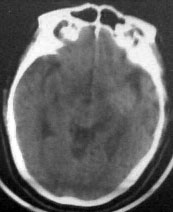

病人男性52岁,一年前曾患脑出血.今突发剧烈头痛,恶心,呕吐..病人家属说病人自去年脑出血以后,精神异常!请大家看看左侧颞叶病灶考虑什么?片子不是很清楚请大家见谅!!左颞叶病灶ct值最高处为85hu

病人此次症状应与右侧丘脑及基底节出血破溃入脑室有关。

左侧颞叶考虑血管畸形,右侧丘脑及基底节出血破溃入脑室

1右丘脑脑出血破入脑室; 2左颞叶avm。如果去年有则更加证明是avm,如果去年没有则可能是钙化尚少,显示不明显. 建议强化

左侧颞叶病灶密度不均,似见点状钙化,支持血管畸形性病变.右侧病变为出血.